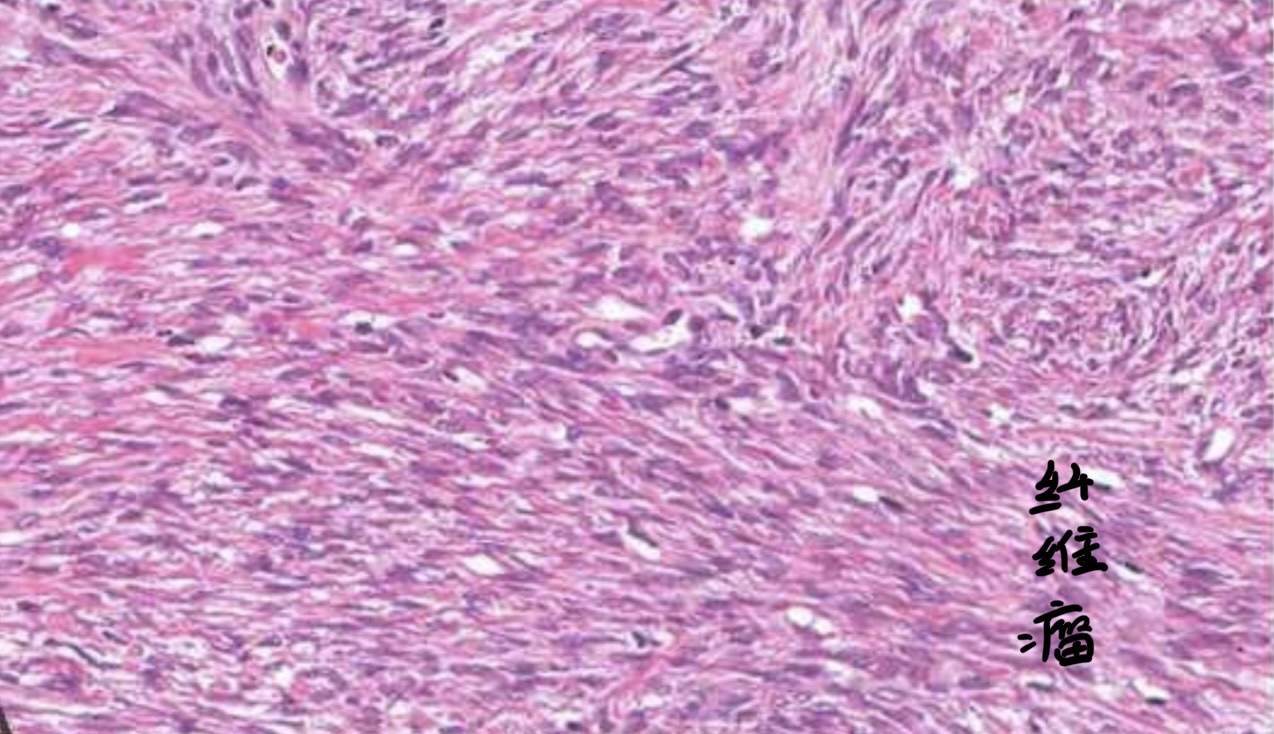

1)纤维瘤

经典的卵巢纤维瘤是梭形的,编织状的,如图: